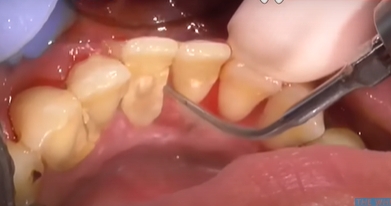

치석은 오랜 시간 쌓이면서 잇몸과 치아 사이를 가리고 있던 돌 같은 물질입니다. 이 치석이 갑자기 떨어지거나 스케일링으로 제거되면 그동안 가려져 있던 치아뿌리나 잇몸 틈이 드러나면서 공간(구멍)이 생긴 것처럼 보일 수 있어요.

하지만 사실 구멍이 생겼다기보단 치석 아래에 있던 원래의 치아 구조가 드러난 것일 뿐이며 다만 이 공간이 음식물이나 세균에 노출되면 문제가 생기므로 그대로 방치하기보단 적절한 조치를 취하는 게 중요합니다.